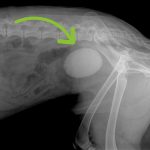

Can Bladder Stones Kill a Dog?

Yes, bladder stones can be potentially fatal to a dog. Left untreated, the stones can cause infection and blockages in the urinary tract that may lead to lethal complications such … [Read more...]